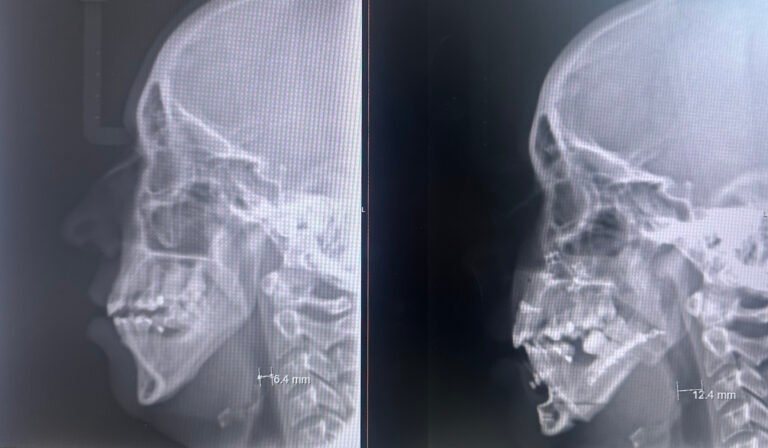

Dois meses após a cirurgia ortognática de avanço bimaxilar e mentoplastia, a paciente, inicialmente diagnosticada com síndrome de apneia do sono grave (102 apneias/h), repetiu a polissonografia, que agora revelou um índice ligeiro, apenas posicional (8 apneias/h). A paciente ficou satisfeita com o resultado estético, sem sintomas noturnos nem diurnos, e deixou de necessitar utilizar o CPAP.